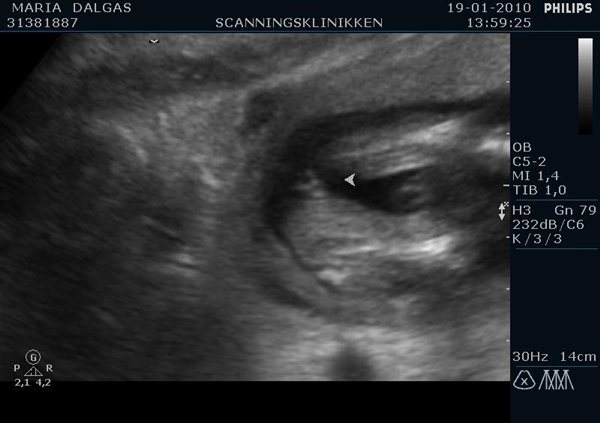

Ja så har man jo været til scanningen i dag og nøj hvor var det vildt I skal næsten selv gætte hvad det er ;P Her er billeder :

Jeg gætter på en pige, hvis det er imellem benene på det første billede.